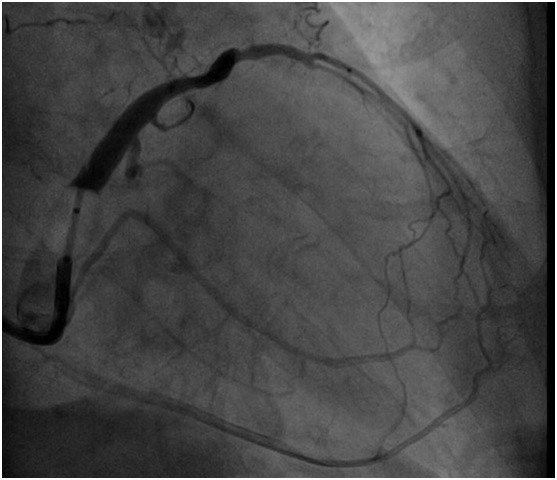

经过充分的术前准备后,由金荣杰副主任医师主刀,林莹副主任医师为助手开始手术。两位医生通过精湛的技术,默契的配合,保证术中患者的各起搏参数测试良好,术中测左室电极阈值为1.2v,QRS波宽度显著缩短至102ms,仅历时2小时15分钟就顺利完成手术。